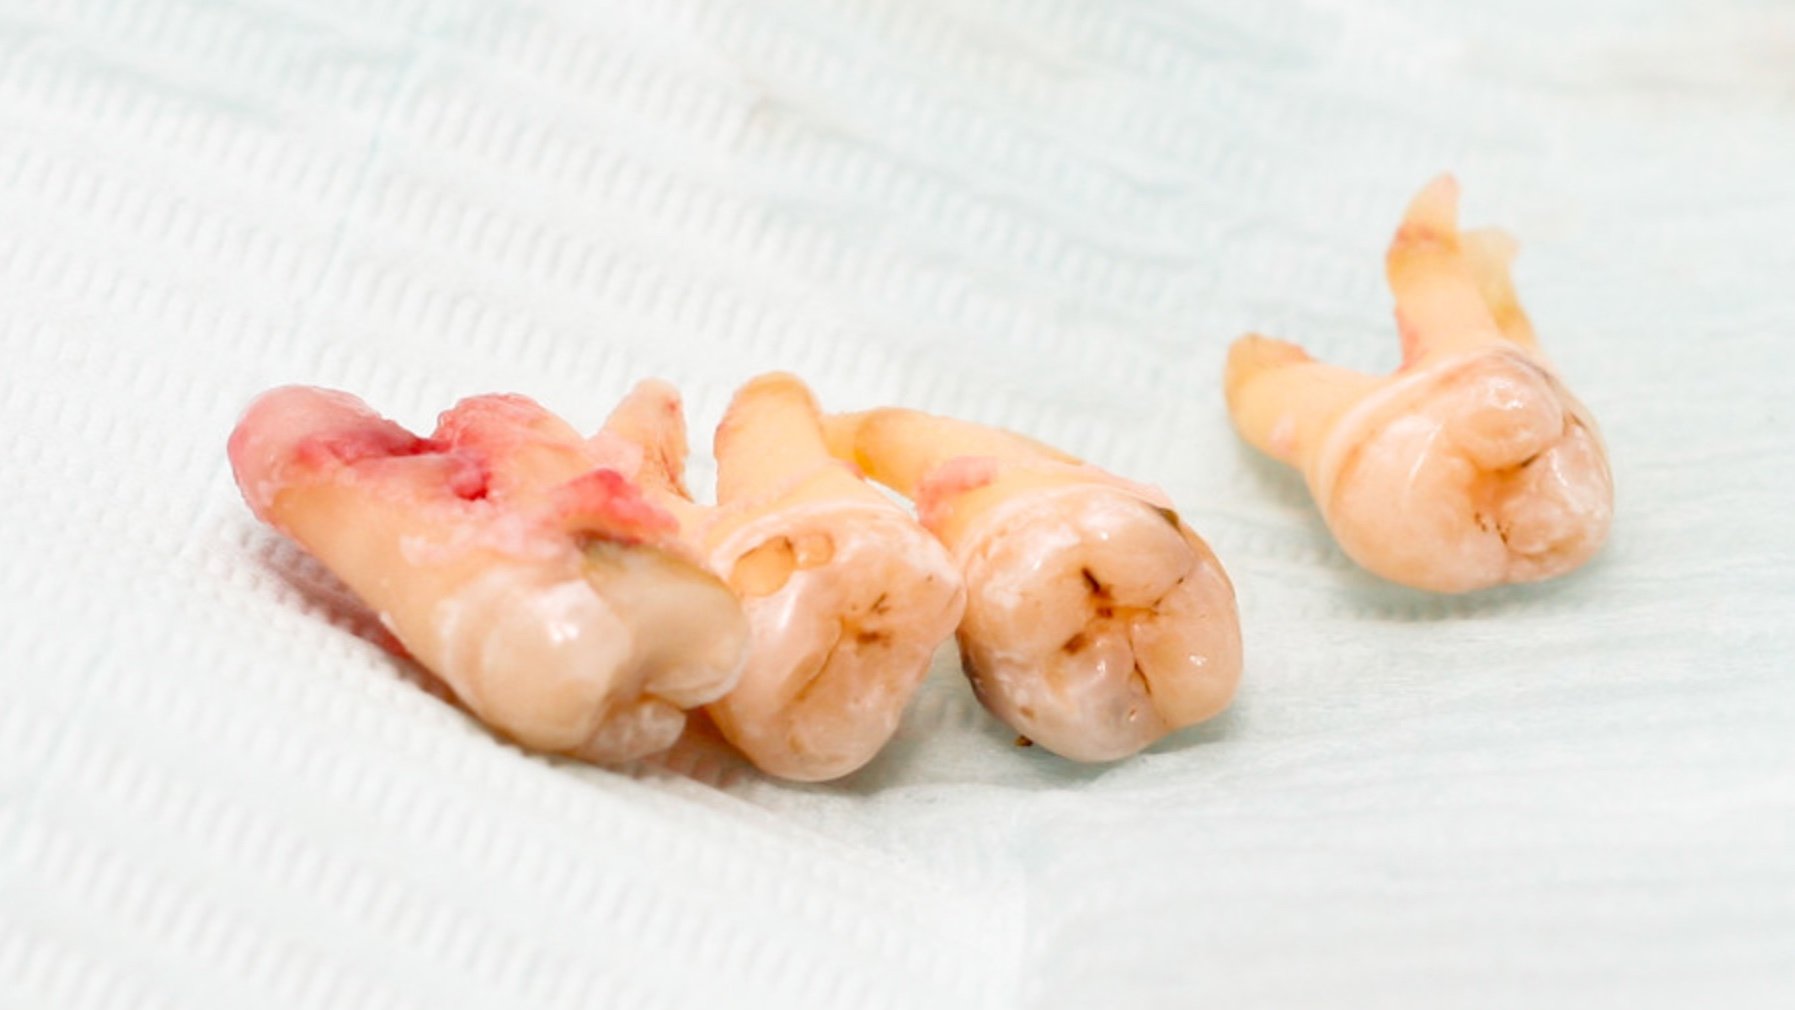

Prosedürün uygulanmasına alıcı sahadaki dişin çekilmesiyle başlanır. Donör sahadan da dişin çekilmesi ve alıcı sahanın donör dişe göre uyumlanması ve dişin alıcı bölgeye sabitlenmesiyle ilk aşama tamamlanmış olur. Prosedür kontrol seansları ve gerekli görülmesi durumunda dişe kanal tedavisi uygulanmasıyla son bulur. Prosedürdeki en önemli aşama, transplante edilecek dişin çekilmesi ve yerleştirilmesi arasında geçen süre olarak düşünülmektedir. Dişin yerleştirileceği alanın dişe göre uyumlandırılması bazen çok uzun sürmekte ve tedavinin başarısını düşürmektedir. Bu noktada tomografi ve 3 boyutlu yazıcılar devreye girmektedir.

Jop P. Verweij ve arkadaşları 2017 yılında yayınladıkları vaka raporunda 3 boyutlu yazıcıların ve tomografinin kullanımını vaka üzerinde sunmuştur. Transplante edilecek olan 3. molar dişin tomografi sayesinde modellemesi yapılmış ve 3 boyutlu yazıcıdan çıktısı alınmıştır. Bu model 3. molar dişin çekilmesinden önce alıcı sahanın donör dişe göre uyumlanmasını sağlanmış ve çekilen 3. molar diş hiç vakit kaybedilmeden alıcı sahaya sabitlenmiştir. Böylece donör diş olabilecek en kısa sürede transplante edilmiştir.